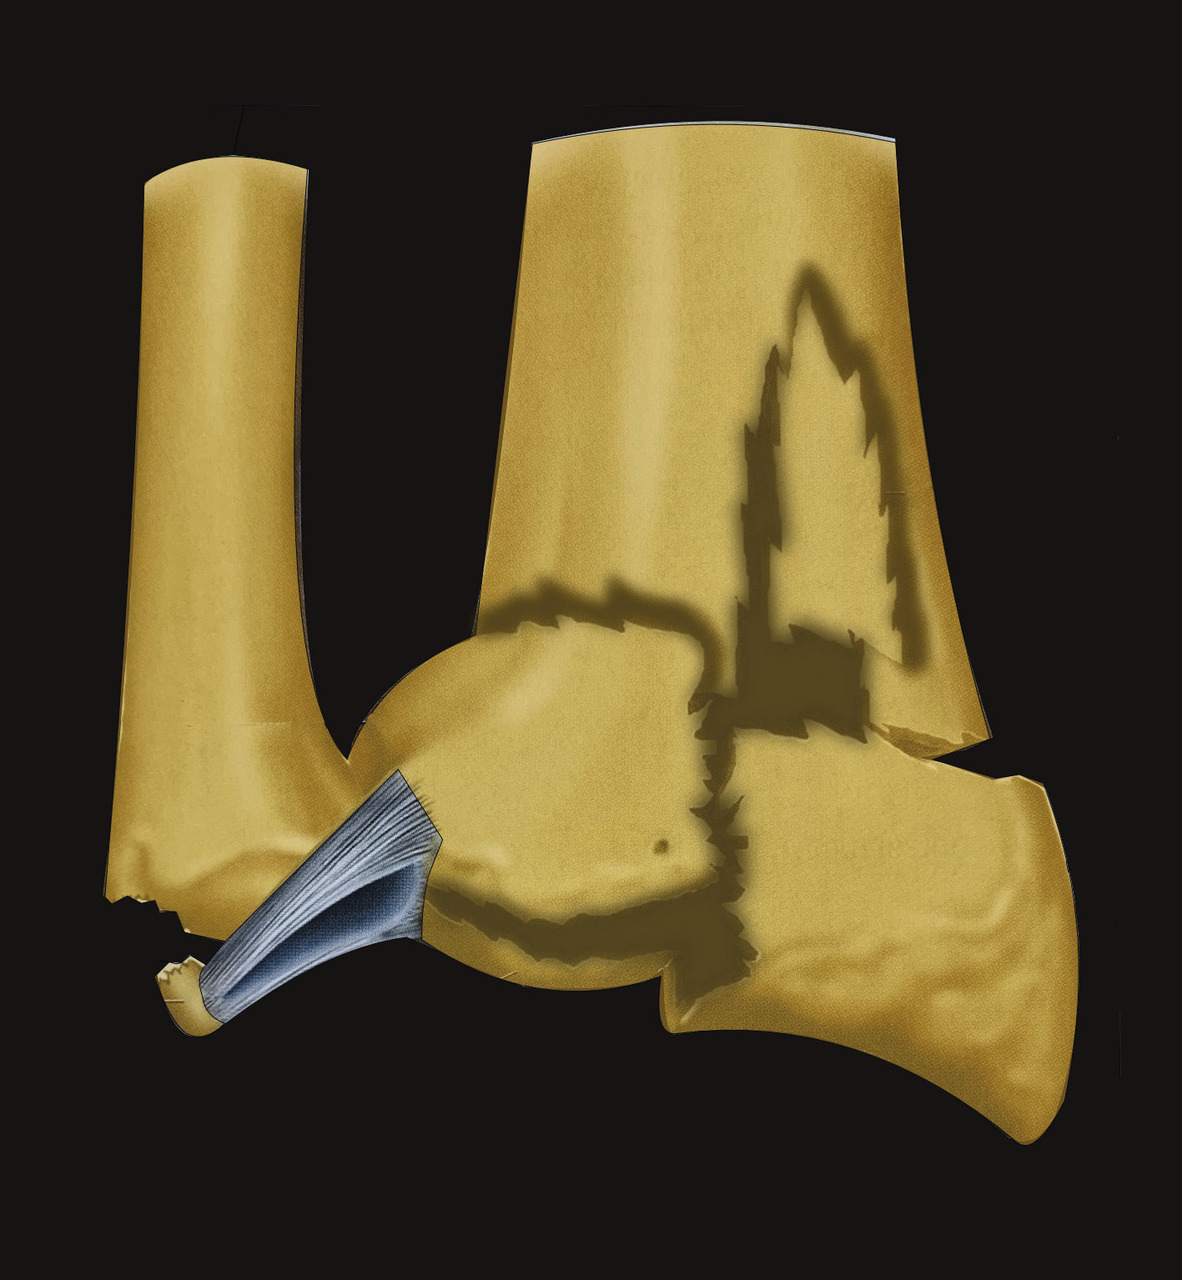

L’analyse de l’épiphyse va permettre de déterminer si la fracture est articulaire ou extra-articulaire. Dans la très grande majorité des cas, la fracture est articulaire. Il existe très fréquemment un fragment postéromédial qu’il est important de rechercher car il faudra le stabiliser lors du traitement. Mais la fracture articulaire peut être plus complexe, en T ou en croix (fig. 9). Enfin, il peut exister des enfoncements de fragments ostéochondraux à l’intérieur du spongieux épiphysaire (appelé par les Anglo-Saxons « die punch »). Sur les fragments épiphysaires s’attachent les ligaments radiocarpiens. Ainsi, une traction dans l’axe permet, par le biais de ses ligaments (effet de ligamentotaxis), de réduire au moins partiellement la fracture. En revanche, les fragments ostéochondraux qui sont enfoncés dans le spongieux n’ont pas d’attaches ligamentaires et ne se réduisent pas par les manœuvres de traction. Il peut arriver que les fractures soient uniquement épiphysaires. C’est le cas des fractures dites marginale antérieure, marginale postérieure et cunéenne externe. Cette dernière est importante à connaître et à dépister car elle s’accompagne relativement fréquemment de lésion ligamentaire intracarpienne, notamment scapholunaire.